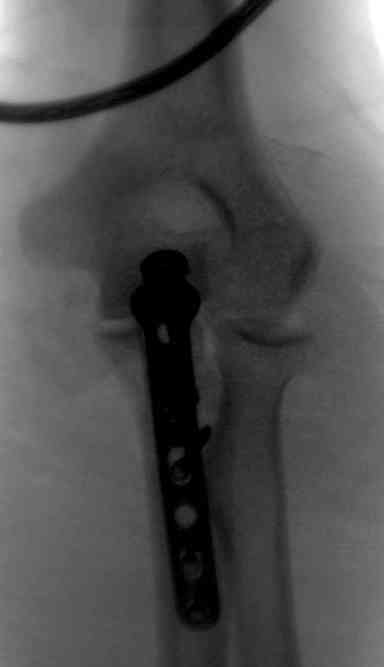

Здесь выставлены несколько случаев и варианты фиксации локтевого отростка, некоторые в комбинации с другими переломами.

2 вариант

перелом локтевого отростка с переломом головки лучевой кости (использованы 2 мм шурупы)